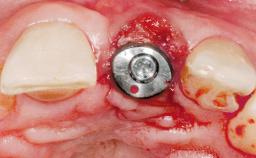

Late Placement of an Implant in a Maxillary Left Central Incisor Site

Type of Implants One-Piece|Reduced-Diameter

Attachment One-Piece|Reduced-Diameter